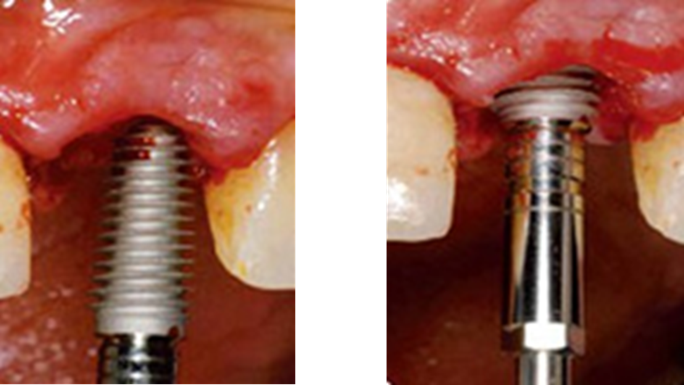

“Immediate loading of single AnyRidge implants

is a highly successful treatment modality. ”

Clinical case: Immediate post-extraction insertion of implant & immediate loading

- Courtesy of Prof. Giuseppe Luongo, Italy -

AnyRidge, immediate loading, single implant, multicenter study, maxillary anterior, Prof. Giuseppe Luongo, single replacement

AnyRidge implant system

Reference

Immediate functional loading of single implants: a multicenter study with 4 years of follow-up

/J Dent Res Dent Clin Dent Prospect 2018; 12(1):26-37 | doi: 10.15171/joddd.2018.005

https://www.ncbi.nlm.nih.gov/pubmed/29732018